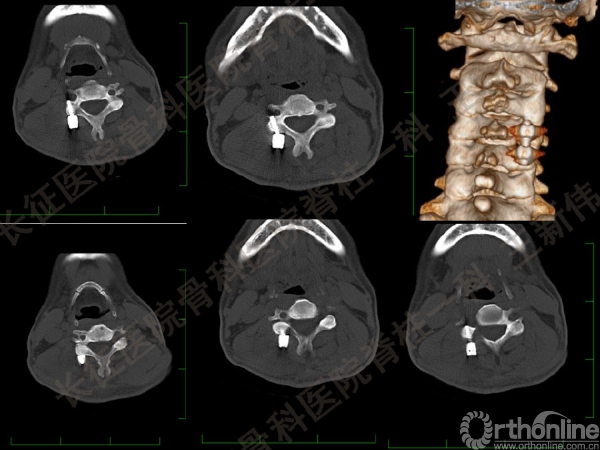

王新伟:颈椎后路通道下手术病例报告及文献回顾

颈椎后路通道下手术有哪些?颈椎后路通道下手术能做哪些事?颈椎后路通道下手术有哪些优势?长征医院骨科医院脊柱一科王新伟副教授通过临床病例报告及文献回顾,给出了他的答案——